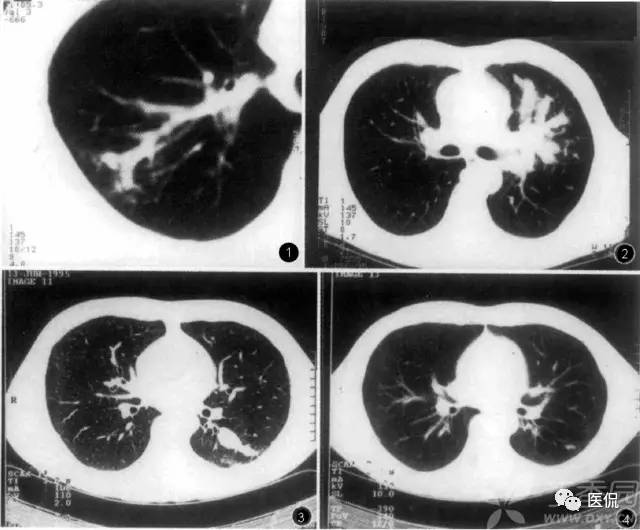

花朵征

花朵征这里主要指传染性非典型肺炎(SARS)的早期表现。该病早期CT表现较有特征性:肺窗上观察,肺血管纹理显著增强,一般在小叶范围渗出,主要为间质渗出,因此密度较淡,往往呈磨玻璃样密度,外形如“花朵”样,即增粗的血管纹理为“花柄”,小叶范围的渗出影像为“花冠”,散布其间的肺血管分支犹如“叶脉”,形成一朵朵根在肺门,朝向胸膜下的含苞欲放的“鲜花”,彼此界限清;病变严重时,“花朵”可融合,形成“花丛”样外观;纵隔窗上常不显影;纵隔淋巴结不大;早期空气支气管征不多见,进一步实变时明显;动态观察,进展迅速,但吸收慢,和临床症状不同步,后期纤维化明显;常在背部坠积性发病,而支气管开口向上的肺叶、段发病相对少见;可以以上肺野发病为主,此时较难与结核鉴别;有少数病人可出现胸腔积液,如治疗得当,吸收很快。典型病例大体可分为间质渗出期、实质渗出期和纤维化期三期。

SARS病毒是一种新病毒,与常见的引起呼吸道感染的其他病毒相比,其毒力强,致病力强,人群普遍易感,因此很容易引起肺部炎症;但其也与其他病毒有共性,早期往往为间质性肺炎,具有间质性肺炎的一般特点。但SARS病毒引起的肺炎,其病理变化较其他常见病毒性肺炎更剧烈,常迅速。造成明显的肺部渗出。发病早期,以间质渗出为主,病毒短时间内大量繁殖,引起血管周围间质及小叶间质渗出,肺泡腔内只有少量的液体和细胞成分,因此病灶密度较淡;肺部明显充血,血管纹理显著增强,以增强的血管纹理为中心,形成“花朵”征或“花丛”征,大体与肺动脉的供血区域形态一致;病变进一步进展时,可有明显的肺泡渗出,从而演变为实质炎,病灶密度增高。此时病理上可见肺泡腔内有大量细胞成分,有时可见透明膜,红细胞。经过治疗后,渗出减轻,部分吸收,肺泡的渗出相对容易吸收,而间质的渗出吸收较慢,容易引起肺间质纤维化,此时病人的自觉症状多数已明显改善,体温业已降为正常,病灶相对静止,可长时间存在肺部阴影。若渗出过多,吸收不良,持续影响通气、换气功能,则可因严重缺氧、呼吸衰竭而导致死亡。由于本病无化脓倾向,因此,整个病程未出现肺实质结构的坏死与破坏,所以也没有形成空洞,这容易和结核鉴别;本病亦少累及大气道,纵隔、肺门淋巴结也不大,因此,一般不引起肺不张,咳嗽、咳痰也较不明显,这与常见的细菌感染引起的实质炎明显不同。可以说,早期非典的CT表现是典型的。

传染性非典型肺炎(SARS)常为双肺发病;多位于两肺中下野胸膜下周边带,但与胸膜之间常有透亮带,较少累及叶间裂或段间裂,不以明确的叶或段分布。